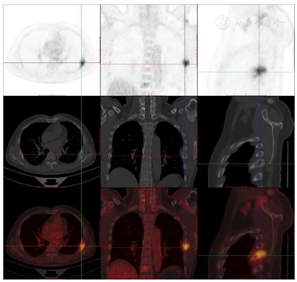

头颅顶可见术后瘢痕,愈合可,后颈可见一长约10 cm术后愈合瘢痕。头颅压痛、包块。发病来,患者神志清,精神可,睡眠可,饮食及大小便正常,体重无明显变化。2021年10月8日行PET-CT示左侧额顶部颅骨术后改变;左侧颞极片状高密度影并邻近骨质破坏,代谢增高(图A);左前纵膈肿块,代谢增高(图B);双肺散在结节,代谢轻度增高(图C);右侧锁骨、左侧第6肋,胸9-腰1、3椎体及其附件骨、双侧髂骨及双侧股骨近端多发混合型骨质破坏,代谢不同程度增高,考虑多发转移瘤(图D,图E,图F);2021年10月10日复查CT示右肺下叶可见结节影,直径约1.5 cm,增强扫描轻度强化;前上纵膈可见类圆形软组织密度影,边界清楚,大小约4.4 cm×3.3 cm,增强扫描轻度强化。于2021年10月11日在局部浸润麻醉下行CT引导下经皮纵膈占位穿刺活检术。病理结果示:肺穿刺组织内见恶性肿瘤,符合转移性间变性脑膜瘤。2021年10月13日MRI示:多发胸椎椎体及附件、所扫及L1椎体异常信号,结合病史,考虑为转移瘤可能。